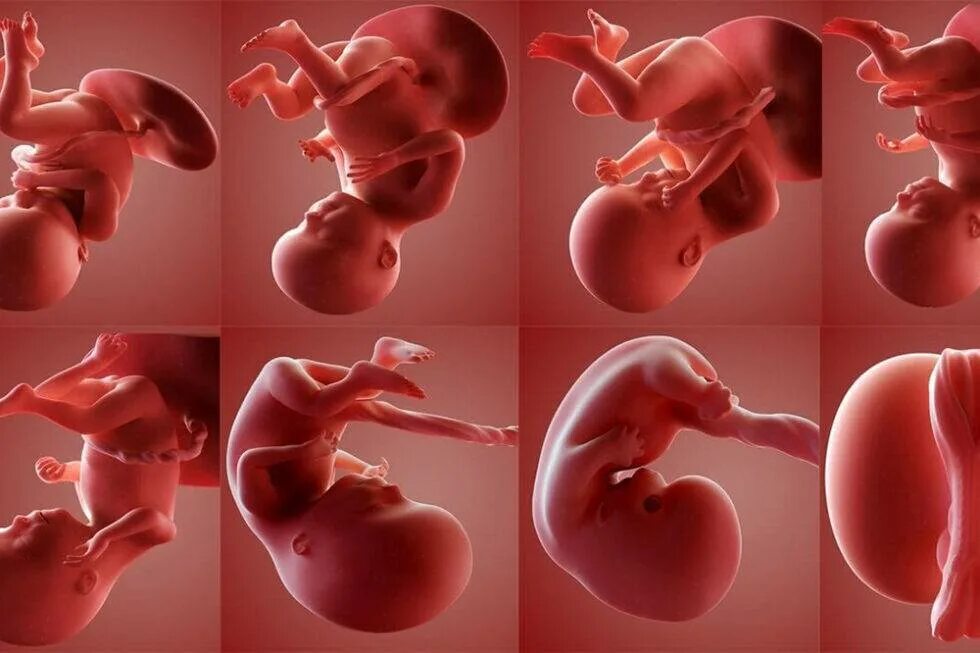

Как выглядит срока